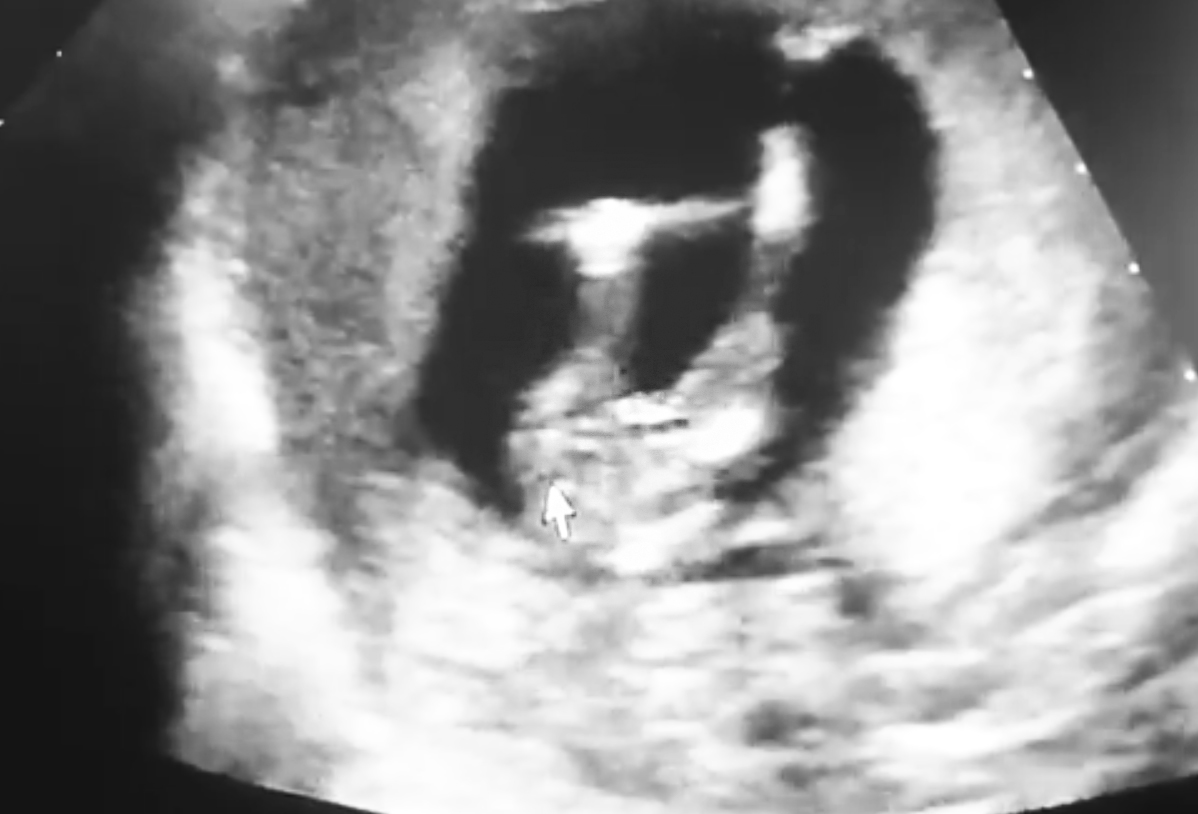

Hello! :D I am Stefania and i was hoping if someone can see/guess if i'll get a boy or a girl.

On the photos i am 14.5weeks. Thanks already!

Boy

I would guess boy

That's so tough I actually thought girl at first but going 50/50 x

For gestation, I would guess girl. I would think a boy would be 90 degrees up at this point. But it does have an angle. I can't say I am confident either way.